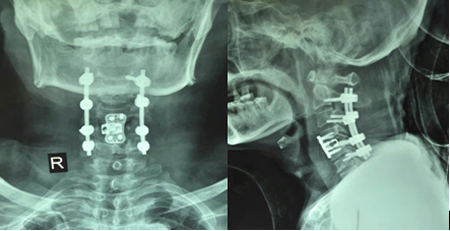

頸椎骨折并脊髓損傷前后路聯(lián)合椎管減壓植骨融合內(nèi)固定術(shù)